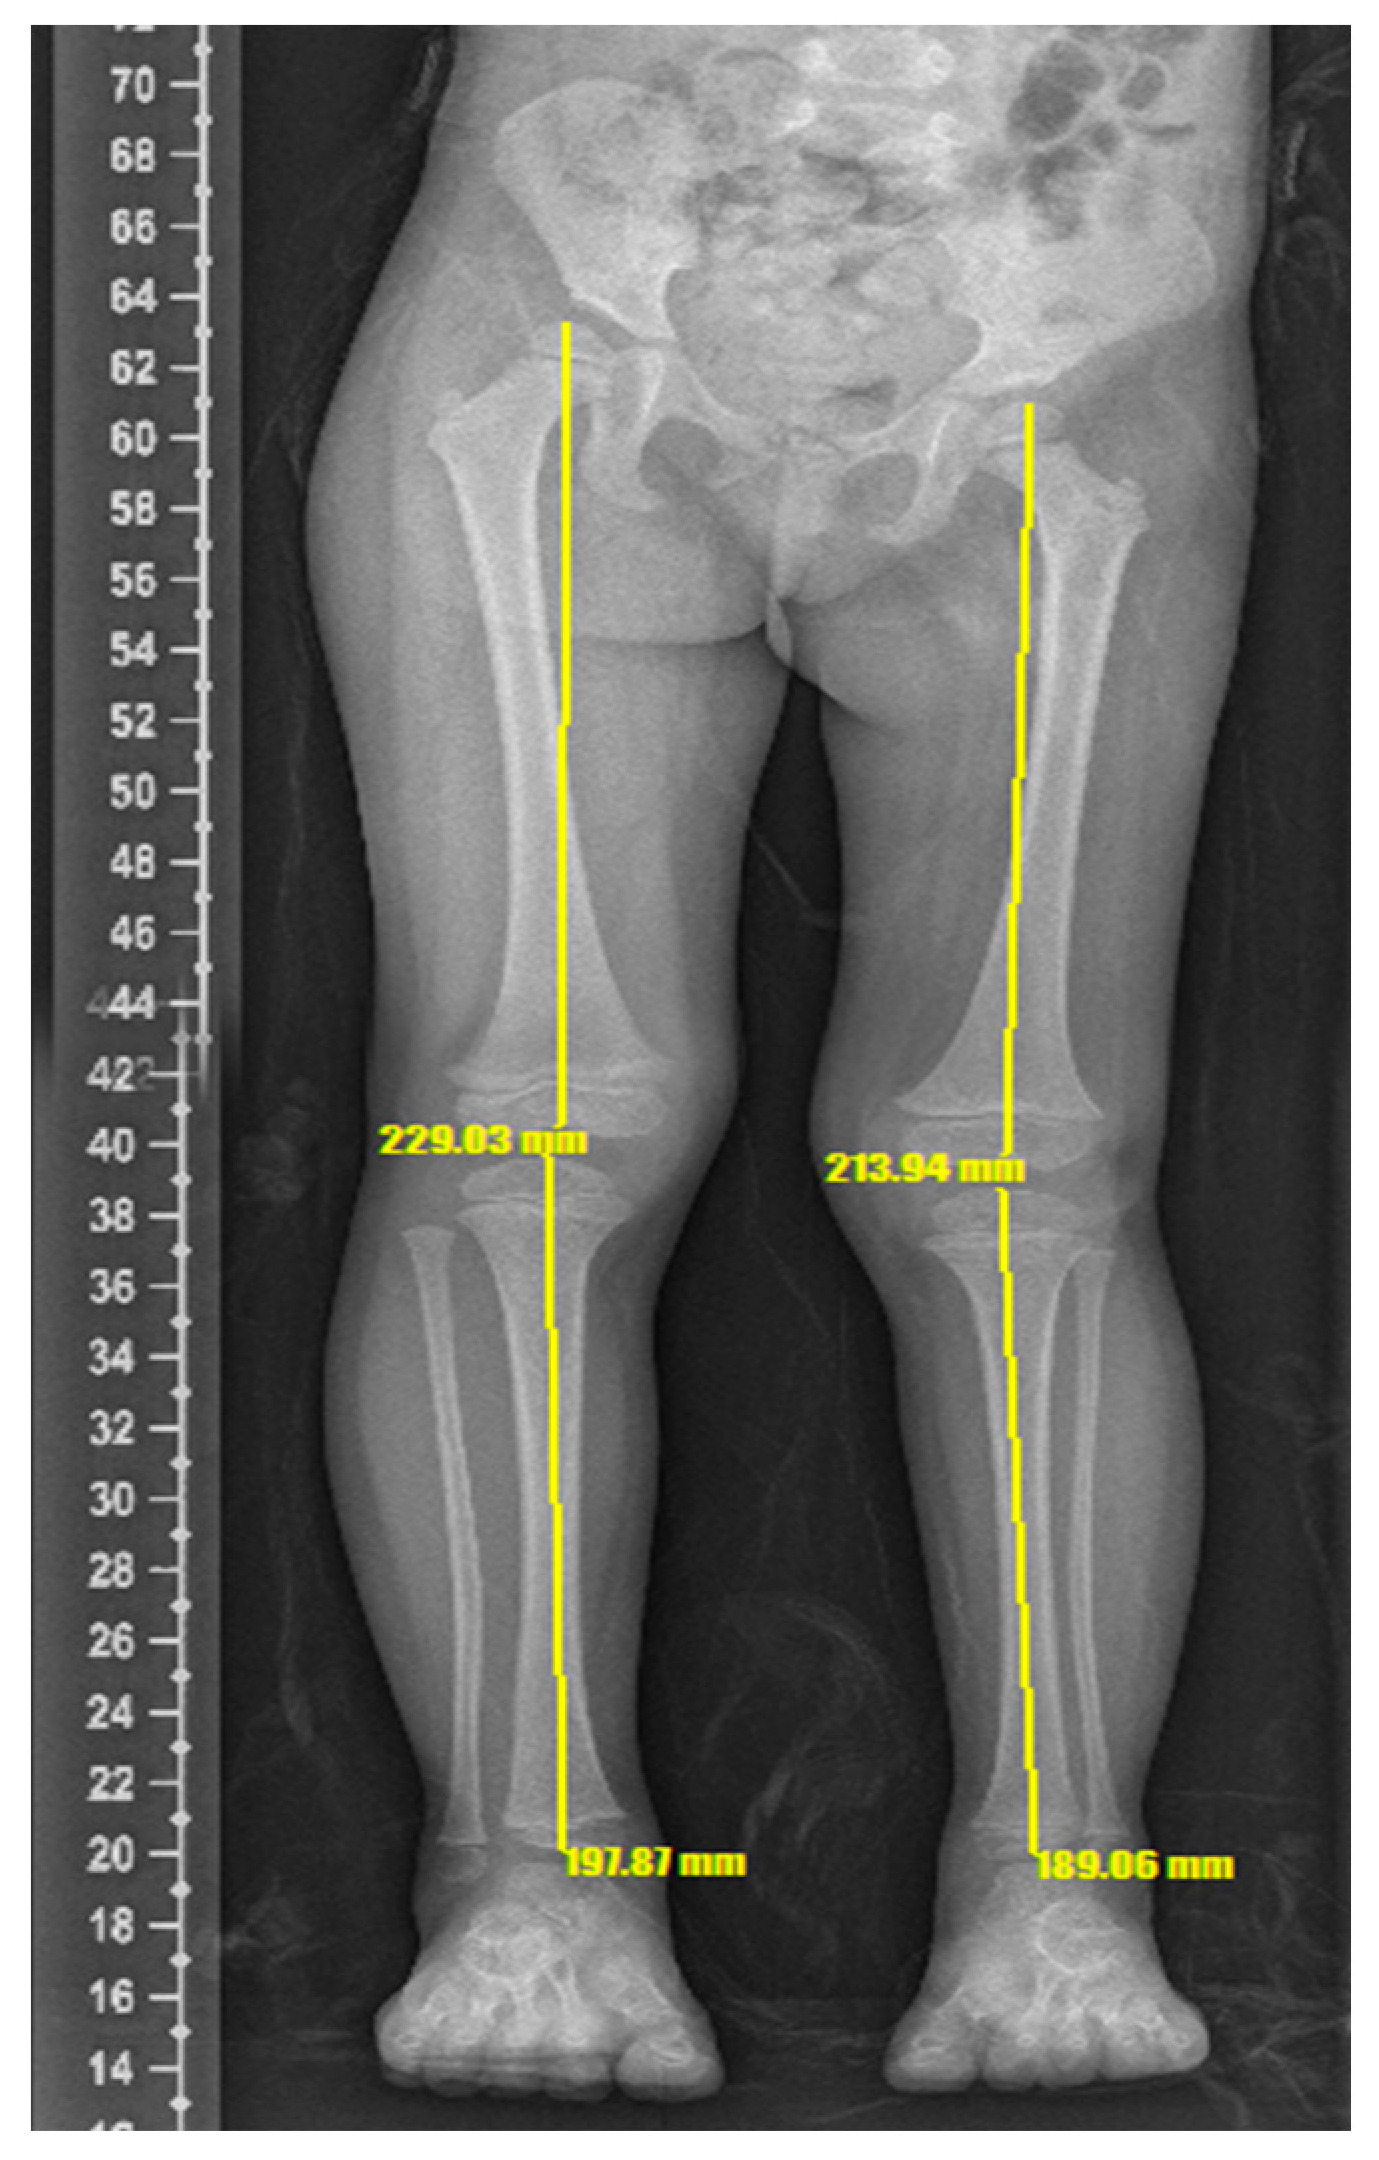

2. Case Description